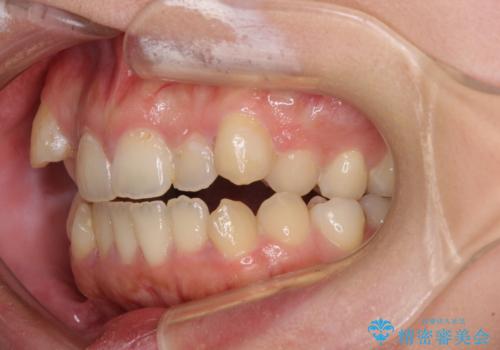

- 八重歯と上下前歯のでこぼこを気にして来院された患者様です。

上下前歯部叢生のスペース獲得のため、上下顎左右小臼歯各1歯(計4本)と全ての親知らずを抜歯して、矯正治療を行うこととしました。